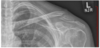

Which shoulder position is displayed? A - AP projection—external rotation B - AP oblique projection—glenoid cavity C - AP projection—internal rotation D - Apical AP axial projection

C - AP projection—internal rotation In this projection of the shoulder, you can see that the lesser tubercle is visualized in profile; this indicates that the projection is the AP with internal rotation (C). The AP oblique projection for the glenoid cavity (B), also known as the Grashey method, would demonstrate an open joint space between the humeral head and the glenoid of the scapula. The AP projection with external rotation (A) would show the greater tubercle in profile rather than the lesser tubercle. The apical AP axial projection (D) is used to open the acromiohumeral space.